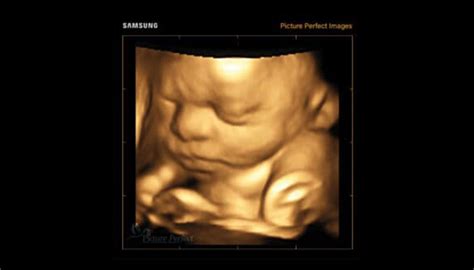

Ecografia 3D și 4D

Ecografia 3D și 4D se realizează similar cu cea 2D, folosind același tip de ultrasunete reflectate, însă din mai multe unghiuri, fapt ce permite computerului să redea o imagine în detaliu a produsului de concepție. Avantajele acestei metode sunt reprezentate de către posibilitatea identificării anumitor anomalii congenitale mai greu detectabile prin metoda clasică 2D: spina bifida (defect de tub neural), palatoschizis sau polidactilia. Ecografiile 4D care permit vizionarea imaginilor tridimensionale în mișcare, în timp real, prezintă recomandare de efectuare în săptămânile 20-36 pentru obținerea unor rezultate cât mai înalt calitative.